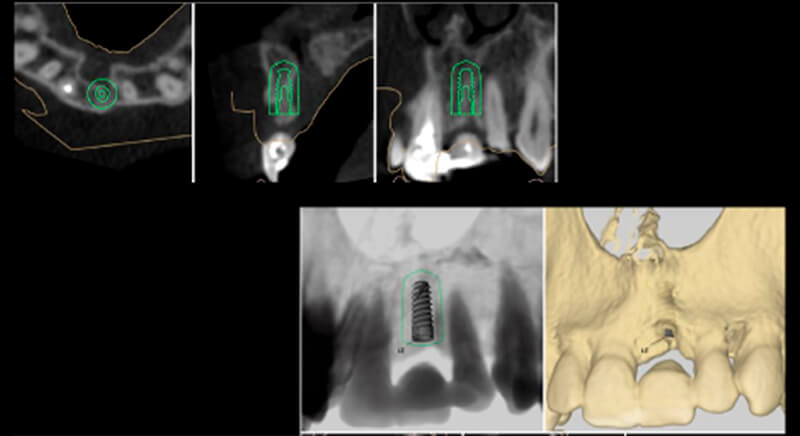

As result of an exhaustive examination a fracture of tooth 1.1 was detected, and although at first a fracture of 2.1 was not observed, it did present movement. Finally, the CT images revealed a radicular apical fracture of tooth 2.1 that meant the tooth could not be saved.

During the digital planning for the implant, with Implant Studio (3Shape) guided surgery software, significant bone defects due to the patient's anatomy were discovered. Placing the implant in the correct position for the prosthesis presented bone dehiscence in the vestibular area, and another bone defect in the palatine area due to the patient's large nasopalatine canal.

This information enabled us to rule out the option of surgery without a flap, as regeneration simultaneous to surgery would be needed, so the idea of using guided surgery was maintained.

The guided surgery was performed by lifting a full thickness mucoperiosteal flap. A Biomimetic Ocean CC implant, diameter 3.5mm and length 10mm, was inserted using the surgical guide in the ideal three-dimensional position and the defects were regenerated with xenograft and reabsorbable membrane, the nasopalatine duct on the palatine side and the area of dehiscence on the vestibular.